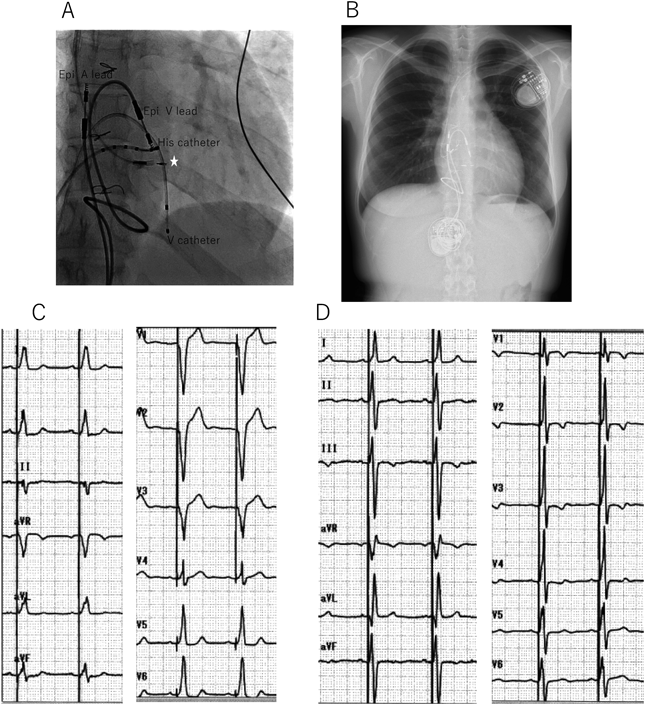

Fig. 6 Para-Hisian pacing in a patient post ventricular septal defect closure with atrioventricular block improved left ejection

A: Fluoroscopic image of right anterior oblique position during procedure. Epicardial ventricular pacing (endocardial leads were placed on the epicardial side) showed pacing failure due to high pacing threshold. His bundle electrogram of own beat detected by His catheter showed HV block. 4.1Fr lumenless lead was screwed to the right ventricular side below HV block site (asterisk). B: Chest X-ray after transvenous pacemaker implantation. Old epicardial leads and device still remained. C: Electrocardiogram before para-Hisian pacing. D: Electrocardiogram after para-Hisian pacing showed narrowing QRS duration. Low left ejection fraction on echocardiography due to chronic right ventricular anterior free wall pacing improved from 42% to 54% after para-Hisian pacing. Epi-A lead, epicardial atrial leal; Epi-V lead, epicardial ventricular lead